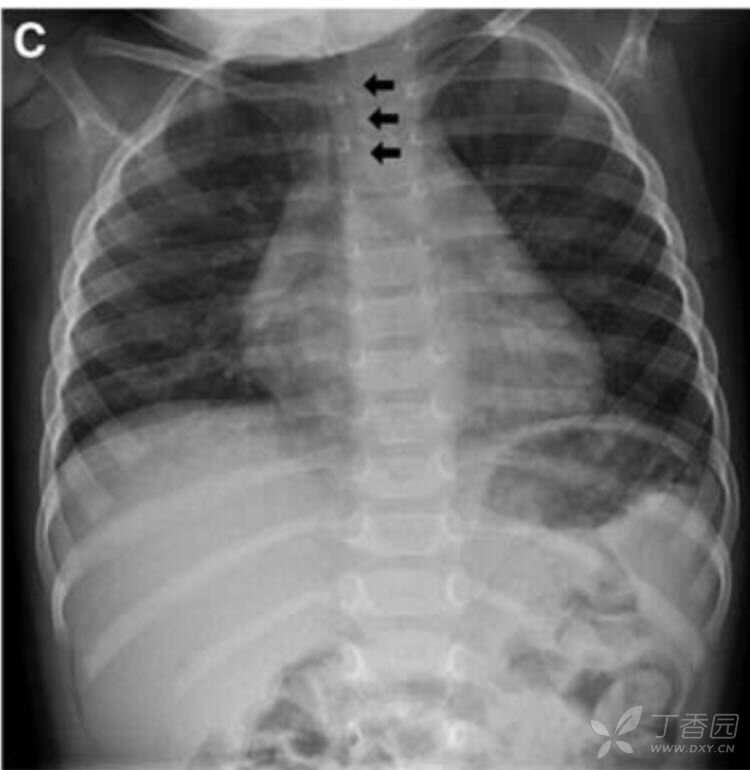

入院后4小时,在安静状态下,胸片检查显示气管是直的(图,C,箭头)。

考虑到这一发现和胸部CT显示没有胸腔内异常,结论是,这种气管弯曲并不提示存在病变,而且与患儿的急性喉炎无关。

认识某些X线的正常结构和异常表现,有一 定的临床意义。婴幼儿气管向右弯曲: 这往往是正常的X线表现。在患儿安静后,再做一次,这种弯曲消失。早年曾有过研究,5岁之前,患儿胸片上的气管向右弯曲并不少见。